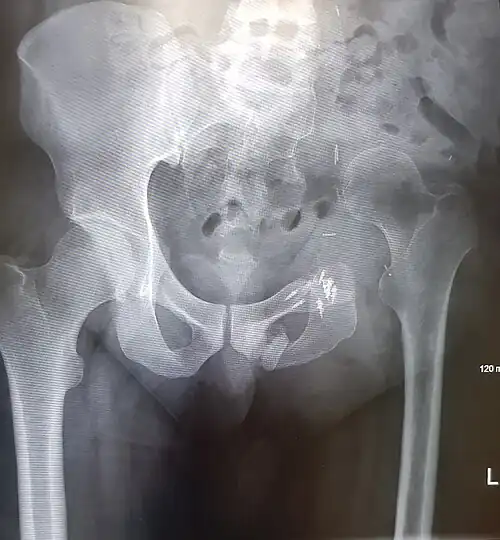

Prior to performing a hemipelvectomy, surgeons must possess detailed knowledge of the pelvic anatomy and its relation to the pelvic tumor.[1] Imaging studies such as conventional radiography, computed tomography, and magnetic resonance imaging help the surgeon visualize the anatomy and its relationship to the local pathology.[1] Surgical oncology techniques are utilized when resecting tumors of the pelvis.[1] Such techniques ensure that adequate resection margins are obtained at the time of surgery to minimize tumor recurrence.[1]

The Enneking and Dunham classification system was developed in 1978 to aid surgeons in characterizing pelvic resections.[1][3][4] This classification scheme breaks down pelvic resections into 3 subtypes: Type I, Type II, and Type III.[1][3][4] Type I resections involve removal of the ilium.[1][3][4] Type II resections involve removal of the peri-acetabular region.[1][3][4] Type III resections involve removal of the ischial and/or pubic region.[1][3]

Images